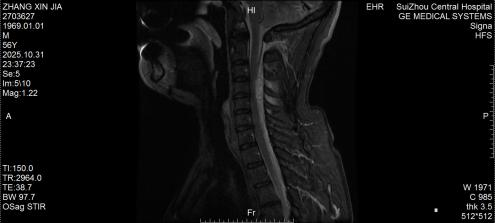

圖1:術(shù)前MRI見椎管內(nèi)積血壓迫脊髓

圖2:術(shù)后MRI見脊髓壓迫解除

10月底的深夜,隨州市中心醫(yī)院急診醫(yī)學(xué)科來了一位特殊患者,突發(fā)劇烈頸痛伴雙手麻木,短短3小時(shí)內(nèi)肢體無力逐漸加重,連簡(jiǎn)單抬臂都難以完成。脊柱外科團(tuán)隊(duì)緊急評(píng)估后行頸椎磁共振檢查,確診為自發(fā)性頸椎椎管內(nèi)出血—— 這是今年該院救治的第5例同類患者。好在急診手術(shù)及時(shí)清除血腫、解除神經(jīng)壓迫,患者術(shù)后恢復(fù)良好,無任何后遺癥,順利出院。